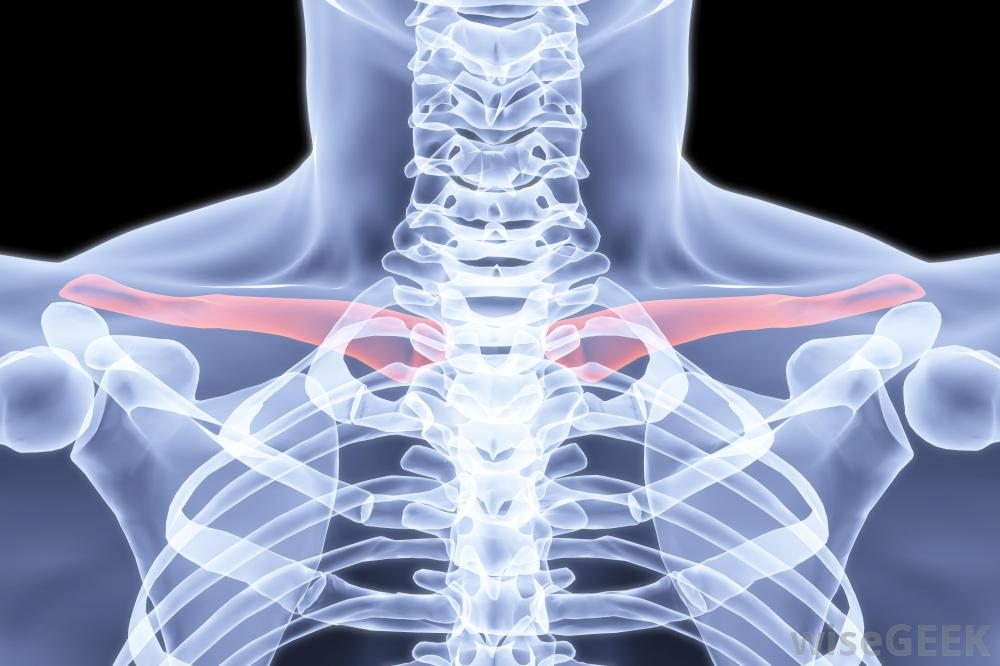

鎖骨,也稱鎖骨,是人體最常見的骨折之一。運動員,兒童,甚至嬰兒從產道出來都會經歷骨折。治療骨折的鎖骨通常不需要手術,但患者可以采取一些措施來妥善治療。為了治療骨折的鎖骨,患者應該去看醫生以確定是否有骨折。固定手臂、使用冷敷和服用止痛藥是治療的常見部分,一旦疼痛消退,進行一系列的運動訓練也可能是必要的人的骨架,包括紅色的鎖骨。如果一個人覺得自己的鎖骨斷了,在去看醫生之前,他應該盡量保持手臂不動。有時,骨折會導致開放性骨折,也就是說,當骨頭穿過皮膚時。如果骨折處有傷口,可能意味著骨頭打破了皮膚,但在患者移動時又重新進入。在這種情況下,患者應就醫,因為手術可能是清理傷口和防止感染的必要手段。射線照片可以向醫生顯示鎖骨是否斷裂鎖骨骨折愈合的時間長短取決于患者的年齡兒童通常在三到四周后痊愈。青少年可能在六到八周后痊愈,但是一個成年人可能要等四個月。一條吊帶或八字形繃帶可能要一直戴著。許多醫生更喜歡吊帶而不是繃帶,因為一個人戴著八字形繃帶時不可能正確地清洗,而且繃帶會比繃帶更不舒服,會引起更多的皮膚刺激。對于鎖骨骨折的病人,可能會開出或推薦不同形式的止痛藥,冷敷20分鐘左右建議每兩小時進行一次,以幫助減輕疼痛和減輕腫脹。疼痛消退后,最好開始移動手臂、手腕和肩膀,以防止其僵硬。醫生或理療師可以教患者進行可以保持手臂的鍛煉活動。在斷開的鎖骨完全愈合之前,不應嘗試運動和其他力量鍛煉。有時手術是治療鎖骨骨折的最佳選擇。這通常發生在開放性骨折或者如果骨頭沒有愈合。在手術過程中,醫生可能需要植入鋼板或螺絲釘。手術也可能是清理傷口和防止感染的必要手段。然而,鎖骨骨折的手術并不常見,而且骨頭通常在沒有任何干預的情況下愈合使用冷敷和止痛藥可以緩解鎖骨骨折帶來的不適。